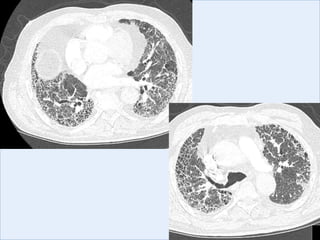

UIP vs NSIP

UIP-like pattern

NSIP-like pattern

Distribution

Honeycombing

Ground glass

Nodules

UIP NSIP